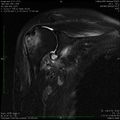

- Différentes lésion labrales post.jpg Alexandre.laedermann

19:53, 26 January 2020

1,918 × 454; 739 KB